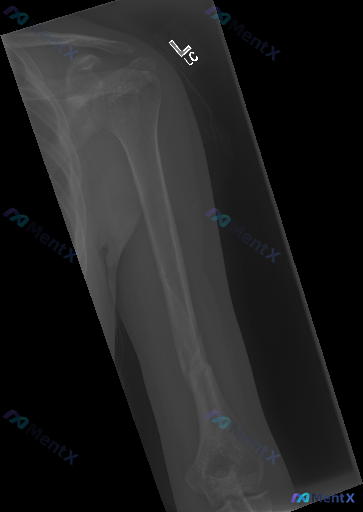

整理到一份左侧肱骨正位X光片的影像资料,结合临床情况和大家讨论一下判断方向: 基本情况 - 提示为成年人(骨骺已闭合) 影像核心表现 - 肱骨干中下段骨皮质连续性完全中断,可见斜形及部分螺旋形骨折线 - 骨折断端有明显向外侧成角移位,同时存在断端重叠(短缩移位) - 骨折周围软组织可见轻度肿胀,密度...